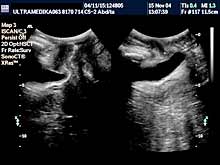

Vrsta i sadržaj pregleda Pregled

podrazumeva pregled tkiva (parenhima) dojki sa procenom limfnih žlezda

i krvnih sudova. Standardni pregled se radi primenom savremenih sondi

veće rezolucije i kompjuterizovanom ultrazvučnom tomografijom (Sono CT

i X -Res), kojom se mogu otkriti promene ispod 5 milimetara.